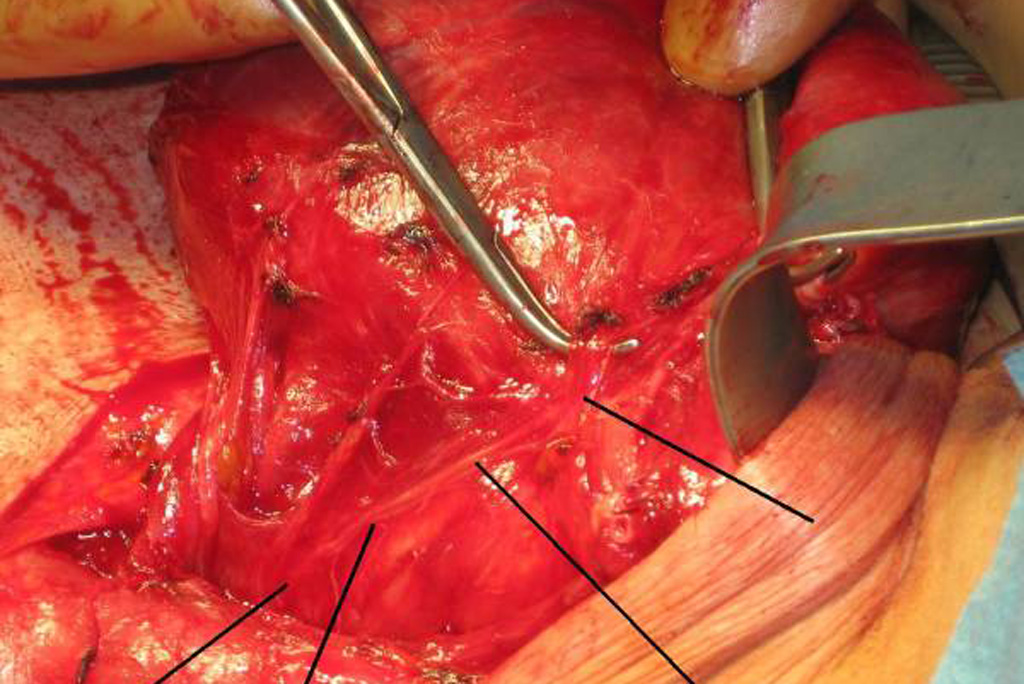

Nervus recurrens links -mit Pfeilen markiert

Intraoperative Komplikationen mit Nervenschädigungen minimiert!

Ein "Nervenscanner", der besonders wichtig zum Beispiel bei Operationen im Bereich des Ösophagus ist, um dort den Verlauf des Nervus reccurens sicher darzustellen, konnte sich die Gesamtinnenstadtkliniken bislang nur teilen. Ein unbefriedigender Zustand, vor allem wenn man im OP feststellen musste, dass das Leihgerät funktionsuntüchtig war.

Eine Initialfinanzierung eines Spenders, der anonym bleiben möchte und eine großzügige Restfinanzierung der Ernst-Wilhelm-Sachs-Stiftung und Vanessa-Sachs-Charity-Foundation konnte das Dilema beenden und das intraoperative Risiko zum Beispiel einer Sprechbeeinträchtigung massiv minimieren! Herzlichen Dank an alle Spender, die diese Anschaffung ermöglicht haben!